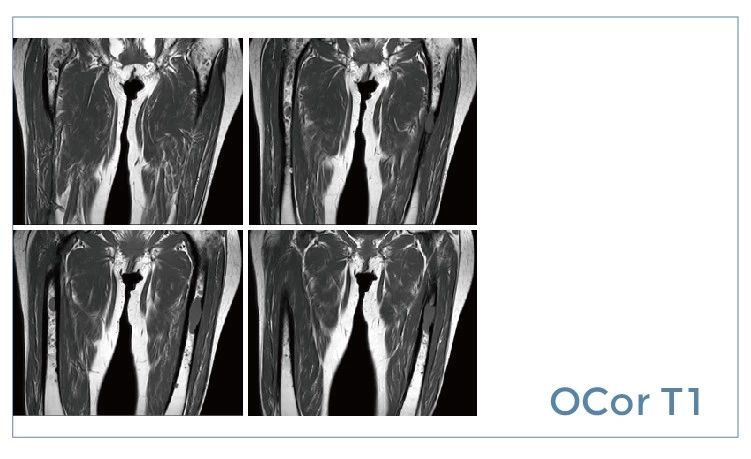

【朗润影像档案】20190712磁共振影像病例结果讨论

【朗润影像档案】磁共振影像病例分享(编号20190712)